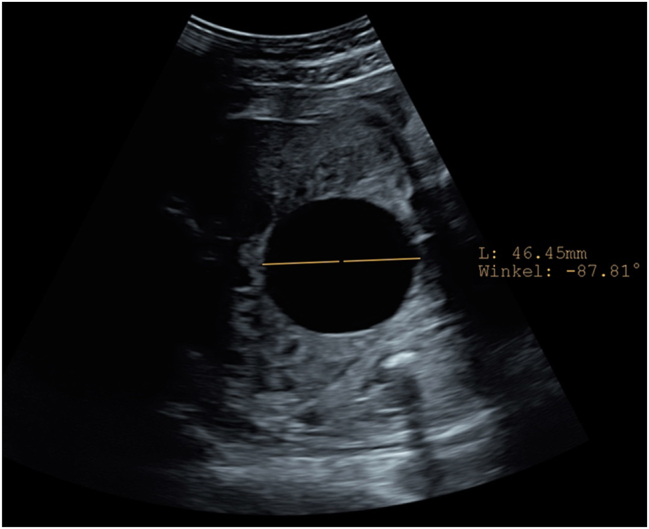

Case presentation: A 18-year old first Gravida at 31 weeks of gestation developed a severe sepsis with progressive hypoxic lung failure and need for intubation. During the ICU-treatment, several opioids were administered for sedation and pain relief. Four days after induction of opioid treatment the ultrasound revealed a decompressed fetal bladder, hematoma and significant ascites. Fetal bladder rupture with urinary ascites was suspected. A caesarean section was performed at 33 weeks of gestation due to massive fetal urinary ascites, fetal deterioration and imminent abdominal compartment syndrome. Adequate ventilation and circulation could only be established after percutaneous drainage of 350 mL of abdominal fluid, that was confirmed to be urine. A defect of the bladder was confirmed by ultrasound. On the fifth day of life, the bladder was closed surgically by pediatric surgery.